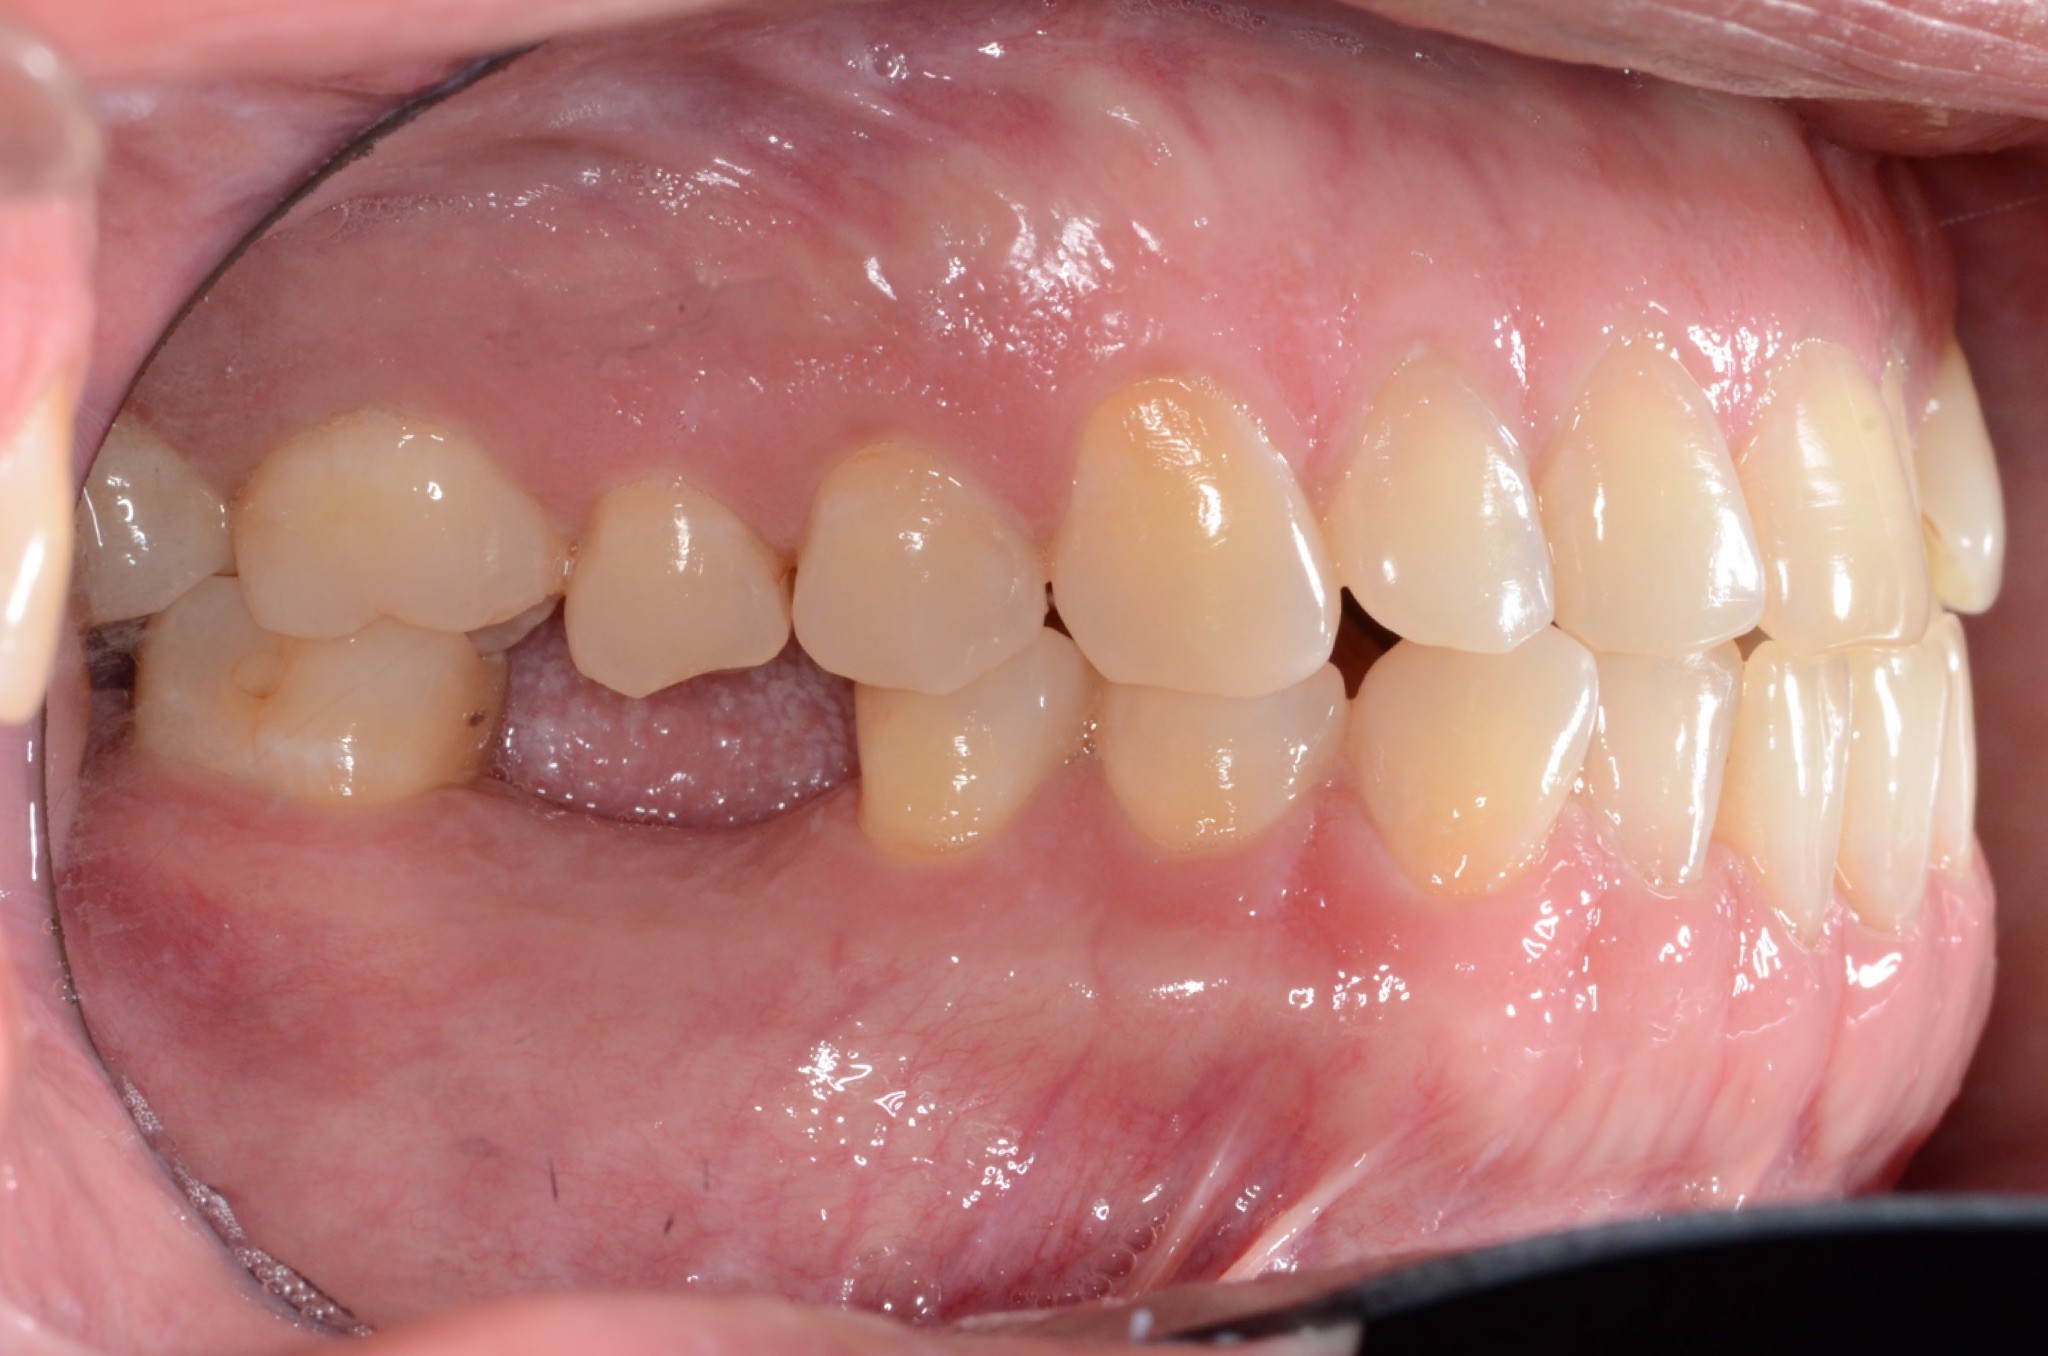

Final results

INTRAORAL